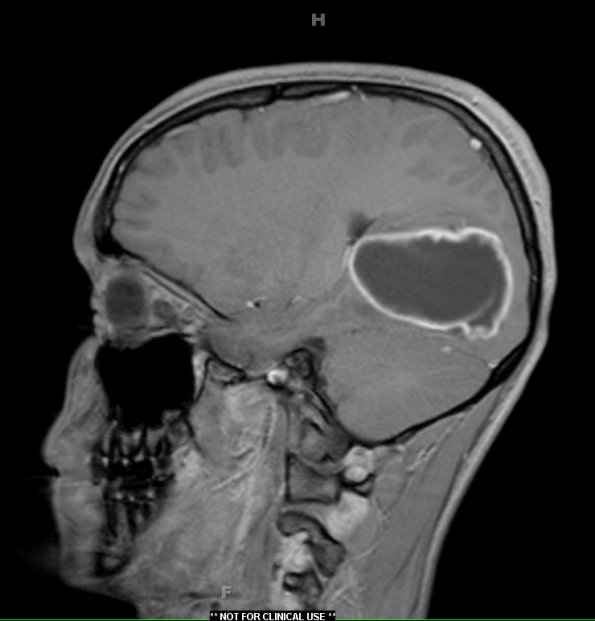

Case 10 ---- 15 year old male, left occipital lobe (no BRAF rearrangement by FISH BRAF preparation) ---- Cystic occipital lobe tumor enhancement demonstrated by T1-weighted image with contrast.